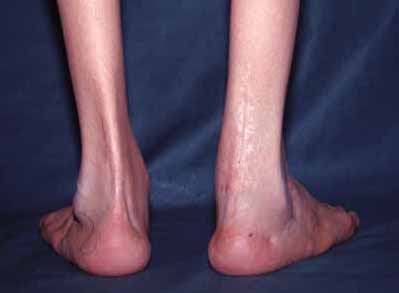

典型的な例をお示しします。

先天性内反足で保存療法後、後方解離などの手術を受けましたが、軽度の変形が残存していました。小学校入学時より野球を始めましたが、その頃から足が腫れたりしています。9才時には足底のしつこい痛みが生じています。写真は14才時のものです。一目では分かりにくいのですが、両側の踵がわずかに内反しています。歩行時体重が足の外側に多くかかっているため足底には有痛性のタコができています。